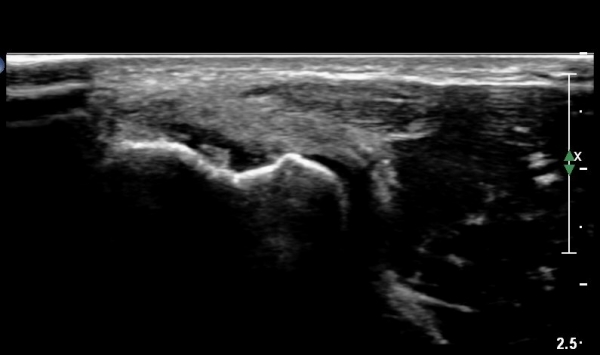

¿Ü»ó°ú Á¾´Ù¸é°Ë»ç¿¡¼­ ªÀº¼Õ¸ñ½ÅÀü°Ç ºÎÂøºÎ¿¡ ±¹¼ÒÀûÀÎ Àú¿¡ÄÚ º¯È­°¡ °üÂûµÊ(»çÁø 1, 2).